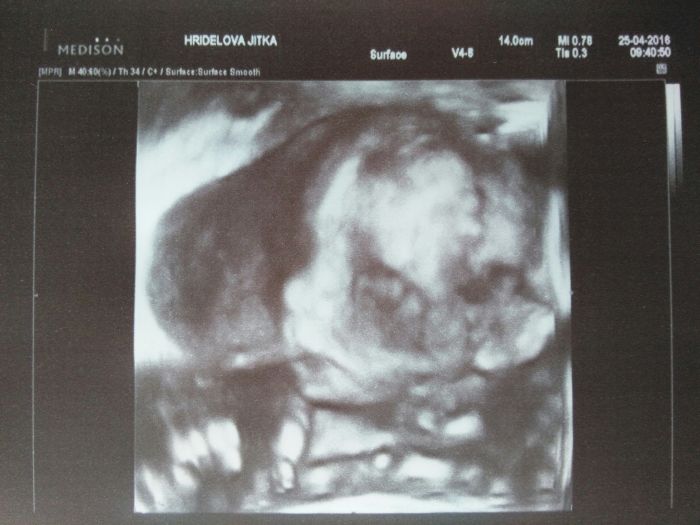

My už máme taky velký utz v 21. tt za sebou. Byli jsme v pondělí. Poprvé byl i taťka. Sice se v tom tak neorientoval, ale líbilo se mu to. Myslím, že pro něj bude lepší 3D

Pan doktor na chviličku přepnul kvůli fotečce na 3D a je to fakt paráda.

Mimčo nám pěkně roste. Je trochu větší. Vše v pořádku a ten pindík se nadal přehlédnout už před tím, než se na něj pan doktor zaměřil

Takže jsme dojatí a šťastní, že je malej v pořádku